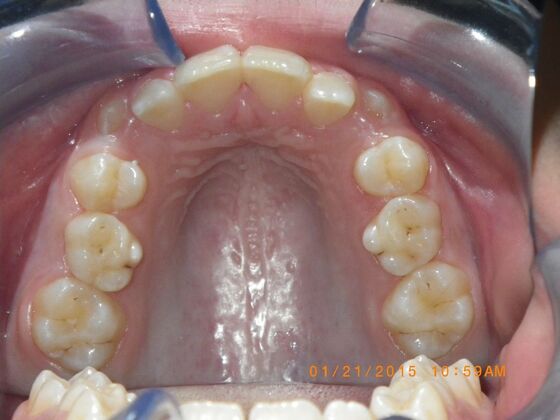

This case presents with a dental midline discrepancy. The upper incisors are tipped toward the palate, which prevents the lower incisors from establishing proper arch form. The upper right molar has drifted forward, causing the upper midline to be skewed to her left. By distalizing the upper left molar, we can correct the midline discrepancy. Lastly, both upper and lower arches need expansion. All of this was completed with conventional straight wire appliances within 2 years.